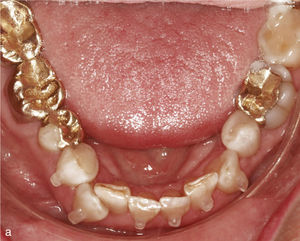

Extracción de dientes anterioresLa falta grave de espacio en el sector anterior hace que en algunos casos sea necesario extraer un diente anterior con el fin de disponer del espacio suficiente para conformar la arcada dentaria y lograr una sobremordida funcional. En la figura 12a se observa la mandíbula de un paciente con falta de espacio en el sector anterior, dientes anteriores rotados y el diente 43 inclinado hacia vestibular. En extracciones realizadas en el sector anteroinferior se colocan sistemáticamente ataches de anclaje en los dientes adyacentes al futuro espacio de extracción. En este caso se colocaron ataches en los dientes 33, 32 y 44, dado que no sólo se cerró el espacio edéntulo, sino que también se realizó una intrusión del sector anteroinferior. La figura 12b muestra el resultado del tratamiento después de la extracción del diente 42 y del cierre del espacio.

Sector anterior de la arcada inferior con dientes rotados y apiñados (a). La conformación de la arcada se realiza mediante la extracción del diente 42 y la colocación de ataches en los dientes 33 a 44. Vista intraoral de la arcada inferior con un aspecto armonioso y el espacio cerrado (b).